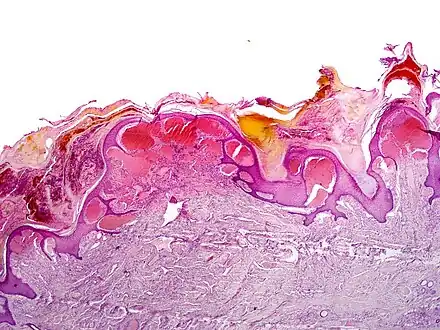

Histology

Angiokeratomas characteristically have large dilated blood vessels in the superficial dermis and hyperkeratosis (overlying the dilated vessels).